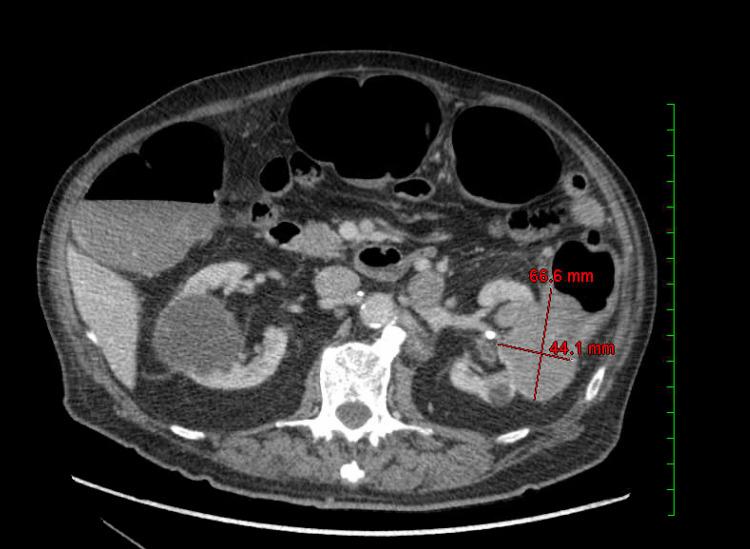

Renal cancer (RC) is known for its diverse clinical presentations and unpredictable behavior. While it often metastasizes to common sites such as the lymph nodes, lungs, bones, and liver, its potential to metastasize to the gastrointestinal tract (GIT) is relatively rare. We report an unusual case of an 87-year-old male patient with a history of metastatic oncocytic renal neoplasm who presented with intermittent rectal bleeding. Colonoscopy revealed a bleeding mass in the sigmoid colon. Biopsy confirmed metastatic renal neoplasm, consistent with prior pathology. Immunohistochemistry was positive for AE1/AE3, CAIX, and PAX-8, supporting renal origin. Recent CT imaging showed enlargement of the left renal mass with direct extension into the descending colon and associated lymphadenopathy. Metastasis of RC in the GIT, especially the colon, is rare and even more so in oncocytic subtypes. This case underscores the importance of considering RC in patients with GI bleeding and a history of renal neoplasm. Early recognition and individualized, multidisciplinary management are crucial for optimal outcomes.

肾癌(RC)以其多样的临床表现和不可预测的行为而闻名。虽然它常常转移至淋巴结、肺、骨和肝等常见部位,但其转移至胃肠道(GIT)的可能性相对罕见。我们报告一例不寻常的病例,一名87岁男性患者,有转移性嗜酸细胞瘤性肾肿瘤病史,出现间歇性直肠出血。结肠镜检查发现乙状结肠有一个出血性肿块。活检证实为转移性肾肿瘤,与先前的病理结果一致。免疫组化AE1/AE3、CAIX和PAX-8呈阳性,支持肾源性。近期CT成像显示左肾肿块增大,直接延伸至降结肠并伴有淋巴结病。RC转移至GIT,尤其是结肠,很罕见,在嗜酸细胞亚型中更是如此。该病例强调了在有胃肠道出血和肾肿瘤病史的患者中考虑RC的重要性。早期识别和个体化、多学科管理对于获得最佳结果至关重要。